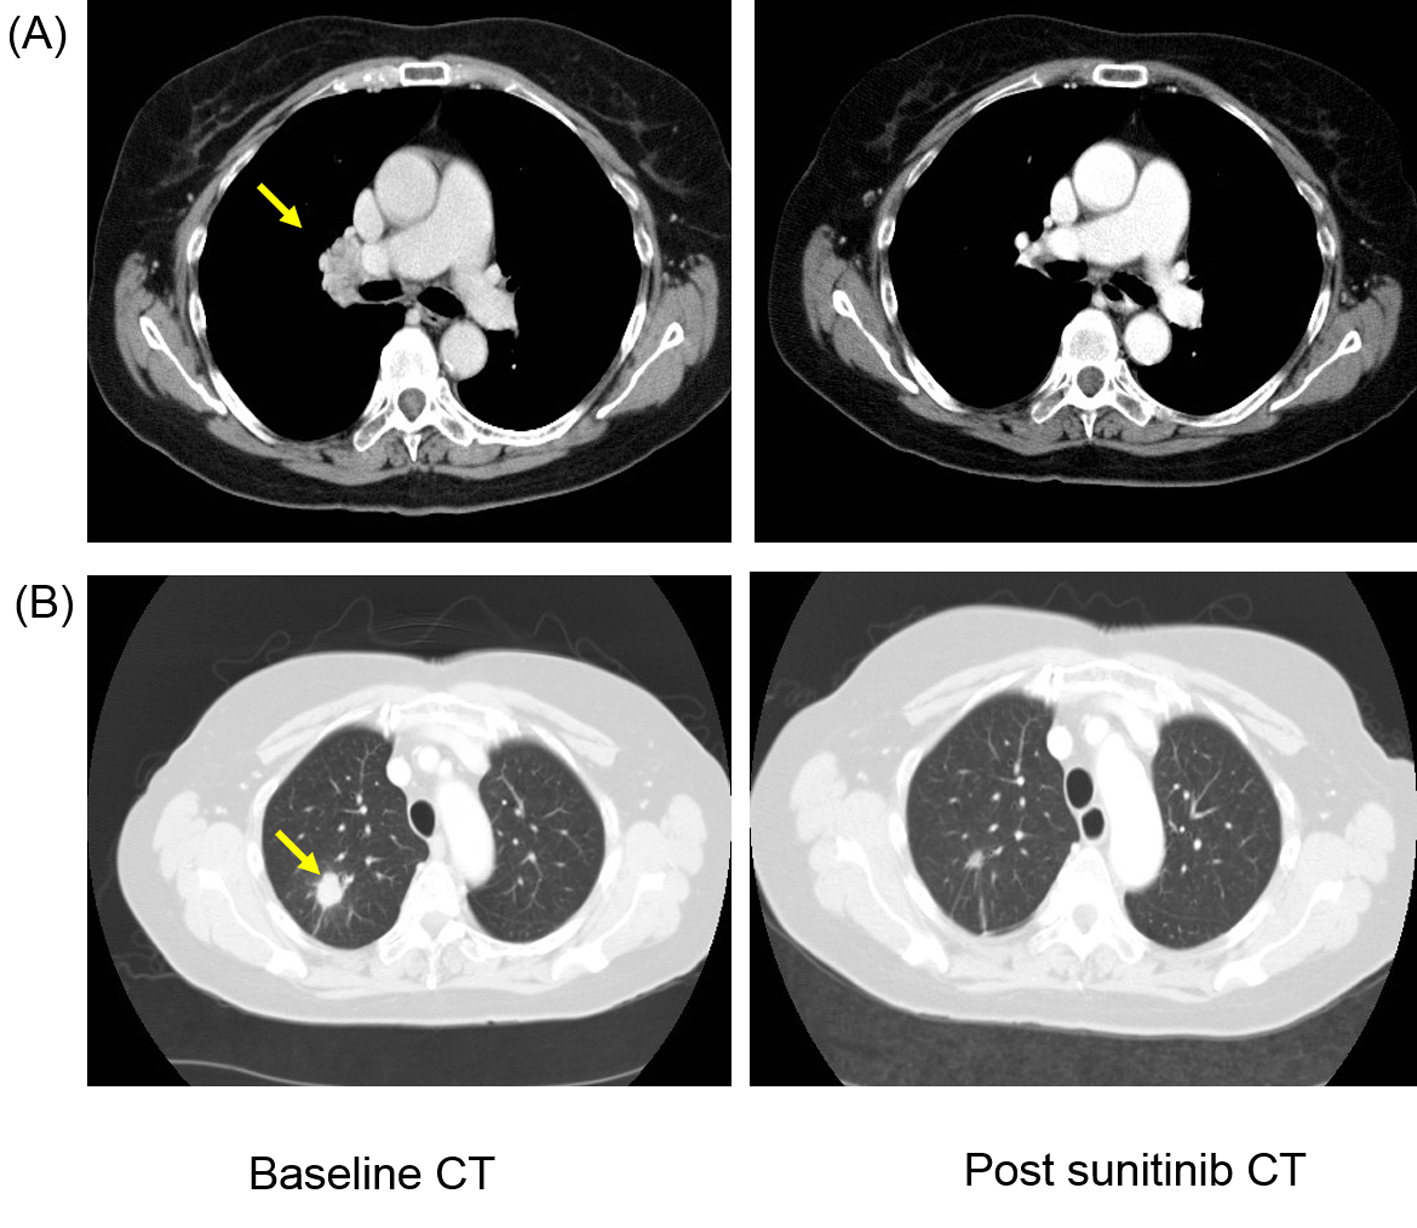

A 73-year-old Caucasian female presented in January 2009 with a large 9 × 8 cm tumor involving the left kidney. She underwent a left radical nephrectomy and post-operative histology showed presence of typical clear cell carcinoma of kidney (Fuhrman grade 3) with involvement of renal vein with pathological staging of T3aN0 (TNM version-7) completely excised RCC. She did not receive any adjuvant therapy. She relapsed in February 2010 when a routine surveillance CT scan demonstrated metastatic lesion in the upper lobe of right lung with associated mediastinal and hilar lymphadenopathy. She was asymptomatic with WHO performance status of one and the hematological and biochemical profile was normal. She was classified as favorable risk based on the Memorian Sloan Kettering Cancer Center prognostic stratification model. She commenced TKI therapy sunitinib at dose of 50 mg/day based on 4 weeks “on” and 2 weeks “off” schedule. She underwent staging CT scan in September 2010 that demonstrated complete response in hilar lymphadenopathy and more than 50% reduction in size of lung metastasis (Fig. 1). She continued on sunitinib but presented in January 2011 with expressive dysphasia, right-sided weakness and generalized seizures and contrast-enhanced CT and MRI scan of brain demonstrated evidence of small multiple ring-enhancing lesions suggestive of multiple brain metastases. The staging CT showed no evidence of relapse outside the brain. At that stage sunitinib was discontinued and she was commenced on dexamethasone with improvement in neurological symptoms. Her case was discussed with neurosurgical colleagues who excluded any local therapy (surgery; SRS) in view of multiple nature of the lesion. Therefore, she was treated with WBRT using dose of 30 Gy in 10 fractions. She tolerated radiotherapy well but subsequently developed radiotherapy-related grade 3 tiredness and fatigue. Subsequently, she was managed with watchful expectancy and repeat imaging in April 2011 demonstrated no evidence of disease progression with stable appearances of brain metastasis.

![]() Click for large image | Figure 1. Patient developed response after first-line sunitinib therapy with complete resolution of (A) hilar lymphadenopathy (yellow arrow) and more than 50% reduction in size of (B) lung metastasis (yellow arrow). |